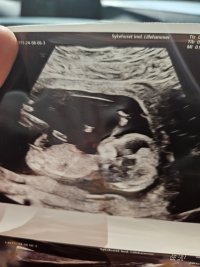

Er da 13+0 i dag, men tenker jeg fortsatt tar mest utgangspunkt i menstermin, det blir minst forvirrende. Jeg var så redd på forhånd, dette var aller første UL bortsett fra en sjekk JM gjorde i uke 8 på et veldig dårlig og lite UL apparat. Heldigvis var det ingenting å bekymre seg for, og alt er i skjønneste orden med lille

Åh det er en fantastisk følelseHer er lille gullet vårt ved gårsdagens ultralydTermin ble satt en dag frem, med andre ord ganske godt beregnet menstermin

Jeg ble mildt sagt lettet med x antall kilo

Jordmor sa at de ikke kunne si noe om kjønn så tidlig, og helt ærlig brydde jeg meg bare om at alt var bra. Da har vi noe å glede oss til ved neste UL

Men er det noen som vil prøve å gjette kjønn?